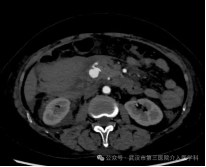

紧急的增强CT检查结果,证实了我们的最坏猜想:肠系膜上动脉的一个分支上,有一个动脉瘤破裂了! 血液正从破口不断涌入腹腔。

精准导航:在DSA透视的引导下,我们像“巡航导弹”一样,将一根细长而柔软的导管,从股动脉一路精准地“行驶”到肠系膜上动脉,最终抵达破裂的动脉瘤分支。

封堵“决堤口”:通过导管,我们向破裂的动脉瘤及其两端释放了数枚微小的 “弹簧圈” 。这些弹簧圈会迅速在破口处盘绕成团,形成一个致密的“塞子”,瞬间堵死破口,让血液无法再流出。

手术成功了! 屏幕上显示,破裂的血管不再造影剂外溢。这意味着,“决堤口”被成功封堵。整个过程,患者体表只有一个针眼大小的伤口。术后,王先生的血压很快稳定下来,脱离了生命危险。